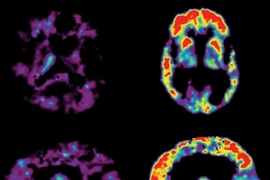

Four years ago, researchers in Sur’s lab found that they could reverse many of the symptoms of Rett syndrome in mice by treating them with a small fragment of insulin-like growth factor 1 (IGF1). In one of the recent PNAS papers, the researchers found that the full-length form of IGF1 also reverses symptoms in mice, which is significant because the U.S. Food and Drug Administration has already approved the full-length form to treat children whose growth is stunted.

To help confirm that this pathway is correct, the researchers treated mice lacking MeCP2 with clenbuterol, a drug that is known to stimulate BDNF production. After this treatment, the lin28a protein was produced at normal levels, restoring the rest of the pathway that leads to IGF1 production. The treatment also improved breathing, motor coordination, and the ability to recall social interactions.